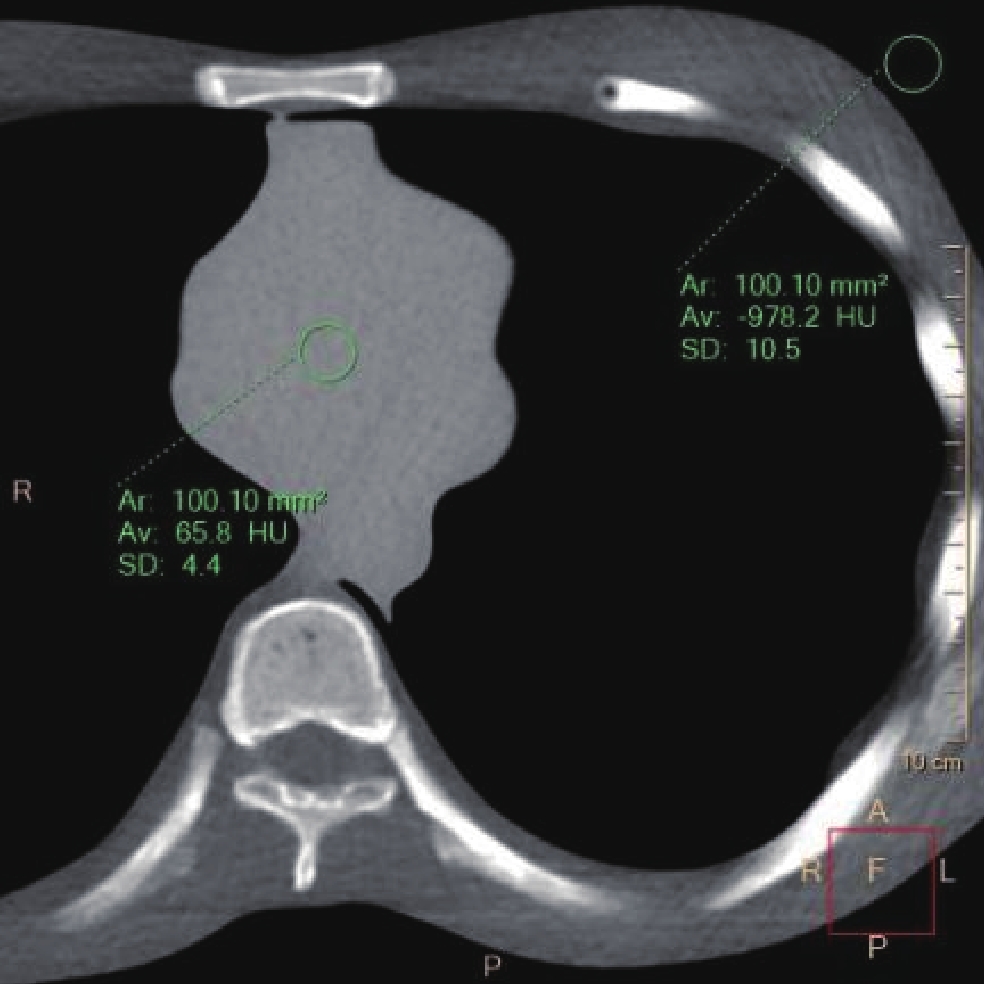

• 摘要: 目的:探讨智能最佳管电压技术SEMI模式(Care kV SEMI)联合迭代算法在冠状动脉检查中钙化积分低剂量扫描成像中的可行性。方法:模体实验采用Care kV SEMI模式和管电流调制技术(CareDose 4D on)。参数设置:SEMI 120 kV(ref.kV分别为100 kV、120 kV),ref.mAs分别为40、60和80 mAs,重建算法分别为滤波反投影算法(FBP)、基于模型的高级迭代算法(ADMIRE)3、4、5。比较各组图像的容积CT剂量指数(CTDIvol)、对比噪声比(CNR)和品质因子(FOM)。回顾性分析30例冠状动脉钙化积分扫描图像作为对照组(ref.kV 120 kV,ref.mAs 80 mAs,重建滤波反投影(FBP)算法),前瞻性采集109例患者冠脉钙化积分CT图像作为实验组(ref.kV 100 kV,ref.mAs 80 mAs,重建算法分别为FBP、ADMIRE 3、5),两组实际管电压均为SEMI 120 kV。记录并计算剂量长度乘积(DLP)、有效剂量(ED)、左主干(LM)和右冠状动脉(RCA)开口层面的CNR、钙化积分(Agatston Score)以及风险分级。由两名高年资诊断医生对患者冠脉图像进行4分法主观评价。对临床研究两组患者冠状动脉CT钙化积分扫描的辐射剂量、钙化积分数值、风险分级以及图像质量差异进行统计学分析。结果:①模体研究结果:实验组辐射剂量较对照组均降低;相同扫描条件CNR 随迭代算法等级增加而增加;ref.kV 100 kV+ref.mAs 80 mAs组4种重建算法下FOM均高于对照组。②临床研究结果:实验组与对照组ED存在统计学差异;实验组FBP和对照组CNR 在LM和RCA两个层面上均无统计学差异;实验组不同重建算法所得Agatston积分间无统计学差异;实验组风险等级Kappa值分别为0.93和0.88,一致性好;两名医生主观评价Kappa值为0.952,实验组与对照组主观评分有统计学差异。结论:BMI 18~25患者进行冠状动脉钙化积分CT扫描时,使用Care kV SEMI模式联合迭代算法对钙化积分和风险分级影响较小,可以有效降低患者辐射剂量。

Abstract: Objective: To explore the feasibility of the SEMI mode of the intelligent optimal tube voltage selection technique (Care kV SEMI) in combination with an iterative algorithm in low-dose calcium score scanning for coronary artery examination. Methods: SEMI mode of Care kV and tube current modulation (CareDose 4D) were used in the phantom experiment. For the SEMI group SEMI 120 kV (ref.kV was 100 and 120 kV), ref.mAs was 40, 60, and 80 mAs. The reconstruction algorithms were filtered back projection (FBP) ADMIRE 3, 4, 5. The volume CT dose index (CTDIvol), contrast-to-noise ratio (CNRp) and figure of merit (FOM) of each group were compared, and a set of parameters were selected for clinical patient image acquisition after a comprehensive comparison. A retrospective analysis of coronary artery calcium score scanning images was conducted, using 30 patients as a control group (ref.kV, 120 kV; ref.mAs, 80 mAs; reconstruction algorithm, filtered back projection, FBP) and a prospective collection of 109 patients with coronary artery calcium score CT images as an experimental group (Care kV SEMI, 120 kV; ref.kV, 100 kV; ref.mAs, 80 mAs). The reconstruction algorithms were FBP and ADMIRE 3, 5. The dose length product (DLP), effective dose (ED), contrast-to-noise ratio (CNR) at the left main coronary artery (LM) and right coronary artery (RCA) ostial level, Agaston score, and risk classification were recorded and compared between groups. The images of the patients were evaluated by two senior diagnostic doctors on a four-point scale. The radiation dose, calcification score, risk classification, and image quality were statistically analyzed using SPSS software. Results: (1) Phantom experiment: The radiation dose of the experimental group was lower than that of the control group. Under the same scanning parameters, the CNRp increased with an increasing reconstruction algorithm level. The FOM of the four reconstruction algorithms in the ref.kV 100 kV+ref.mAs 80 mAs group was higher than that in the control group. (2) Clinical study: There was a statistically significant difference in ED between the experimental group and the control group. There was no statistically significant difference in CNRc between the experimental group with FBP and the control group on the LM and RCA levels.There was no significant difference in Agaston score between the experimental and control groups. The consistency of the risk grade in the experimental group was good, with kappa values of 0.93 and 0.88, respectively. There was no statistically significant difference in FBP and CNRc between the experimental and control groups at either level. The subjective evaluation results of doctors A and B were consistent, and the kappa value was 0.952. There was a statistically significant difference in the subjective evaluation between the two groups. Conclusion: Care kV SEMI combined with an iterative algorithm has little effect on the calcification score and risk classification, and it can effectively reduce the radiation doses of patients with a BMI of 18−25.